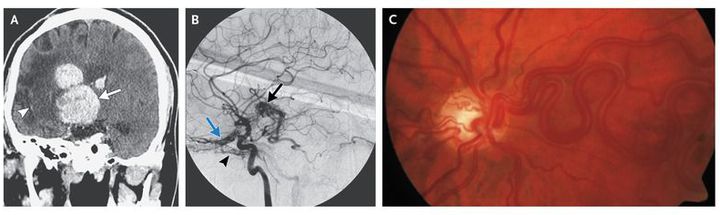

A 28-year-old man with a childhood history of spontaneous intracranial hemorrhage presented with a new onset of seizures and loss of consciousness. At the age of 10 years, he had undergone partial resection of a right-sided intracranial arteriovenous malformation, which resulted in left hemiplegia. He was completely blind in the right eye, and visual acuity in the left eye was 20/20 with a temporal hemianopic field defect. Computed tomography without contrast material revealed a new acute intraparenchymal hemorrhage (Panel A, arrow) adjacent to an area of encephalomalacia (Panel A, arrowhead) on the right. Angiography showed a residual arteriovenous malformation (Panel B, black arrow), with an additional intracranial arteriovenous malformation located in the inferior aspect of the anterior cranial fossa (Panel B, blue arrow) to the right of the midline, which was fed by branches of the ophthalmic artery and right inferolateral trunk (Panel B, arrowhead). Ophthalmoscopic examination revealed a retinal arteriovenous malformation in the right eye (Panel C), whereas the left eye was normal. The patient underwent surgical correction of the intracranial arteriovenous malformation. At follow-up 10 months later, his vision remained unchanged. He had persistent left hemiplegia and was continuing to receive antiseizure medication.